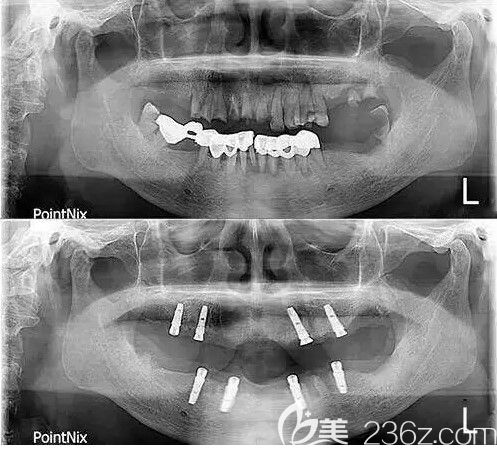

种牙前和种牙后的CT片,用了4颗种植体弥补了我多年来的腐烂牙:↓↓